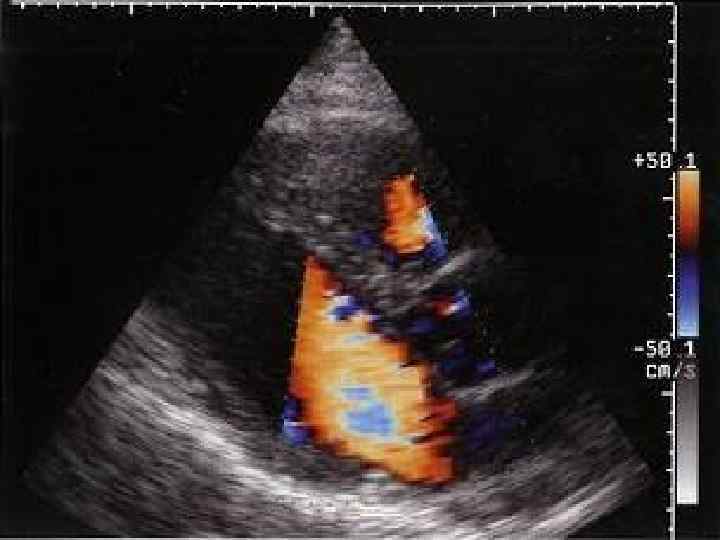

Систолическая функция ЛЖ Метод допплер-Эхо. КГ Определение УО, ФВ и других гемодинамических показателей с по мощью допплер Эхо. КГ основано на измерении величины объемного кровотока через аорталь ный клапан. С этой целью из верхушечного доступа в позициях двухкамерного или пятикамерного сердца проводят допплер локацию выходного отдела ЛЖ в импульсном режиме и получают систолический спектр линейной скоро сти кровотока в выходном отделе ЛЖ. После этого в режиме двухмерной Эхо. КГ, зарегистрированной из парастернального досту па по длинной оси ЛЖ, в середине систолы измеряют внутренний диаметр фиброзного кольца аортального клапана (D), автоматически рассчитывая площадь поперечного сечения корня аорты.